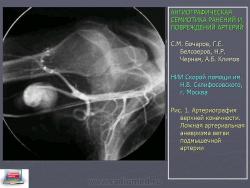

Ложные аневризмы встречались наиболее часто - в 38% наблюдений. Они могут быть различных размеров и конфигурации. На ангиограммах они представлены экстравазацией контрастного вещества в ограниченную полость за пределы сосуда (рис. 1).

Рис. 1. Артериография верхней конечности. Ложная артериальная аневризма ветви подмышечной артерии